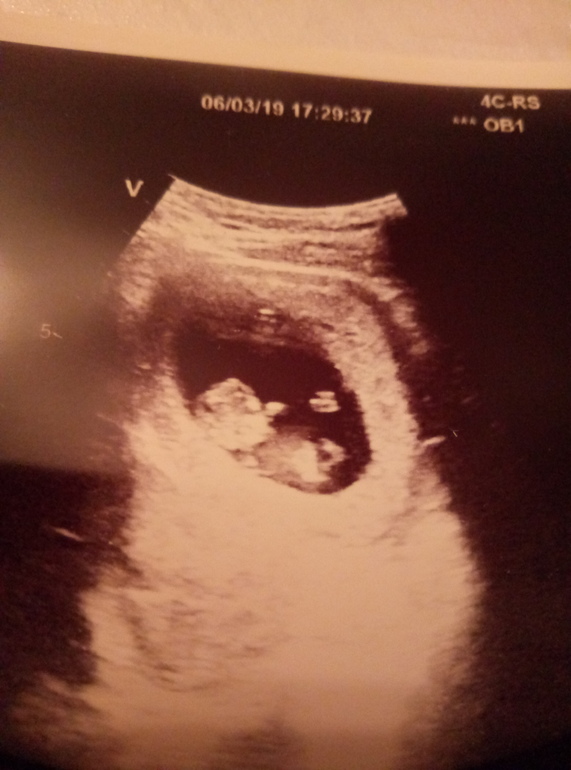

Узи ровно 10 недель

Узи делали абдоминально.

Сразу увидела,что малыш двигает ножками и ручками. Очень активно. Узист сказала сразу видно,что нервная система развивается хорошо. Видно было лицо,профиль. Уже человечек. Активно подвигался 5-7сек,а потом заснул.

Пя в верхней трети матки,сб +,хорион по задней стенке 8мм. Длина шм 39мм. Внд пя 39мм, ктр 34мм.

К счастью,нет отслоек и чего то не

хорошего. Старалась себя беречь,как могла. Успокоилась до скрининга) Один снимок особенно смешной. Ручкой сделал себе такой носик.